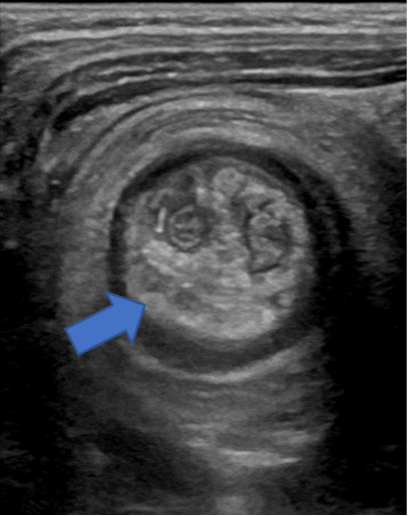

Intussisception appears as a non-compressible, target-shaped mass with concentric echogenic and hypoechoic rings on the transverse view and as a “pseudokidney” or “stack of pancakes” on the longitudinal views (Fig. 4 and Fig. 5 a,b,c).1,3,4 The important characteristic appearance on transverse scan is the presence of the central/eccentric and hyperechoic mesenteric fat, that is pulled with vessels and lymph nodes into the intussusception by the intussusceptum; which differentiates from other entities, such as bowel hematoma, stool, bowel wall edema, mass, or even a psoas muscle.9 Doppler ultrasonography can also be useful to detect and evaluate blood flow. The absence of flow is a sign that surgical reduction may be necessary.4

(Figure 6a: Left) (Figure 6b: Center) (Figure 6c: Right)

Figure 6a-6c. Right lower quadrant ultrasound, transverse (a) and longitudinal views (b). (c) Layered 3.4 cm appearance mass is identified in the right lower quadrant, interposed hypo/hyper echogenic layers, with central hyperechoic mesentery fat, representing the intussusceptum (arrow).